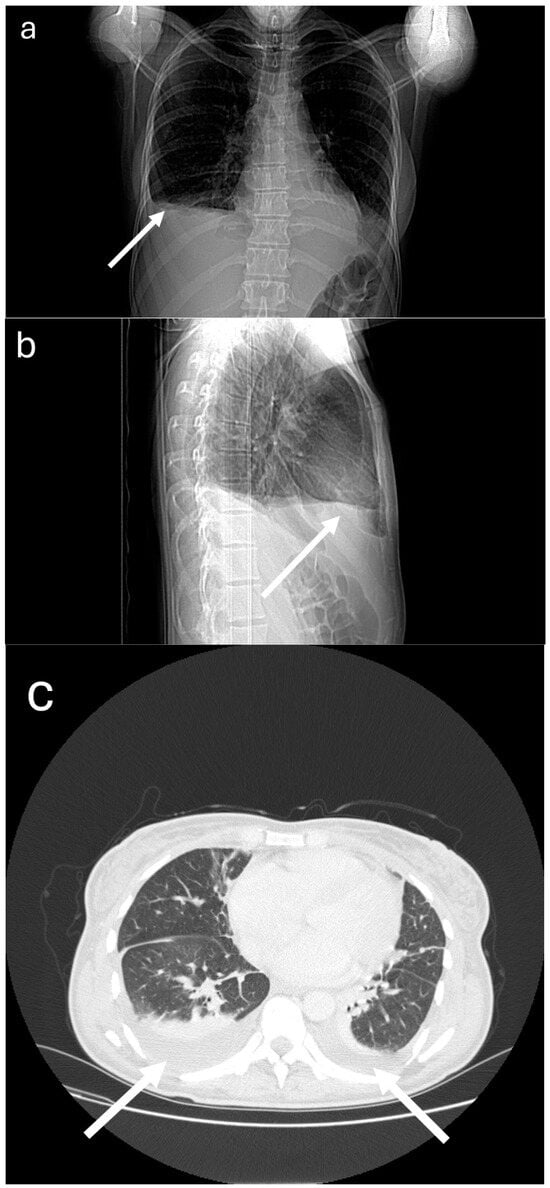

2. Case Presentation